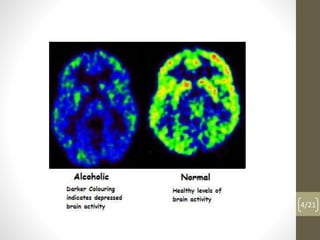

The document discusses alcoholism, including what it is, its health effects on the brain, liver, pancreas and stomach, and the social problems associated with it. It provides details of a case of a woman who drank and drove, and discusses why people drink alcohol, the cycle of alcoholism, and how to quit drinking alcohol by admitting it's a problem, getting help from others, changing attitudes and rewarding progress. It also mentions Alcoholics Anonymous and its role in helping people achieve sobriety.